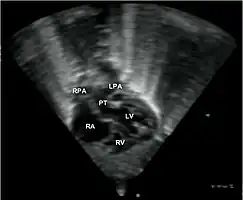

Echocardiogram: An echocardiogram is an ultrasound of the heart which accurately assesses the heart’s structure and function, and can show the specific features of TGA, if present. This imaging modality allows for the definitive diagnosis of TGA to be made. [8]

Abbreviations: LV and RV=left and right ventricle, PT=pulmonary trunk, VSD=ventricular septal defect, PS=pulmonary stenosis. - Echocardiogram in transposition of the great arteries. This subcostal view shows the left ventricle giving rise to a vessel that bifurcates, which is thus identified as the pulmonary artery.

Abbreviations: RA=right atrium, RV=right ventricle, LV=left ventricle, PT=pulmonary trunk, LPA and RPA=left and right pulmonary artery.